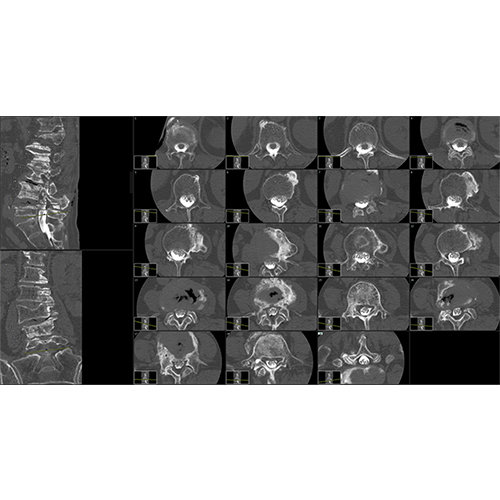

BrainVoyager starts by automatically assembling images into 2D and 3D functional and anatomical multi-slice projects.

Parametric and non-parametric statistical maps may be superimposed both on the original functional scans as well as onto T1-weighted 2D or 3D anatomical reference scans. Time courses of selected regions-of-interest (ROIs) are available both in 2D and 3D representations. Statistical maps may be computed either in the 2D or 3D representation since structural as well as functional 4D data (space x time) are transformed into Talairach space. This allows you to compare activated brain regions across different experiments and across different subjects

Segmentation of tissue (e.g., isolating the brain, differentiating gray and white matter) is performed using region-growing methods, filter operations as well as the application of 3D templates. Using the mouse it is very easy to explore a 3D volume with superimposed pseudocolor-coded statistical maps in a four-window representation showing a sagittal, coronal, transversal and oblique section. Based on a (segmented) 3D data set a three-dimensional reconstruction of the subjects' head and brain can be calculated and displayed from any specified viewpoint using volume or surface rendering.

Volume rendering is performed with a very fast ray casting algorithm; lightning calculations are based on Phong-shading. Surface rendering of reconstructed surfaces is performed using OpenGL. Using texture mapping, a reconstructed surface (e.g., head or brain) may be sliced in real time, showing both surface and volume data at the same time. Initial polygon meshes serve as the basis for surface finding, cortex inflation and cortex flattening computations.